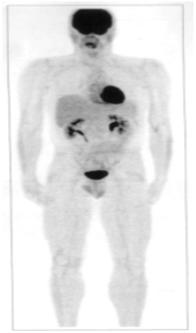

Рис. 6. Скан всего тела мужчины с нормальным распределением ФДГ (чёрный цвет). Активность интенсивно аккумулируется в головном мозге, в фарингеальной области, в слюнных железах, в левом вентрикулярном миокардии (вариации), мочевыводящей системе и мочевом пузыре. Умеренная активность наблюдается в печени, селезёнке и яичках.